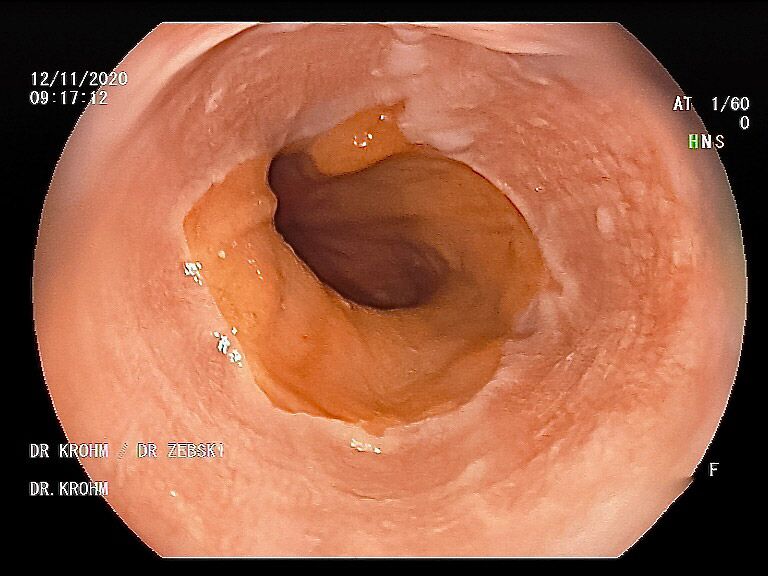

Mit einer Gastroskopie werden Speiseröhre, Magen und Zwölfingerdarm (der oberste Teil des Dünndarms) untersucht. Dazu wird ein geschmeidig biegsames, schlankes Endoskop mit eingebauter Digitalkamera durch den Mund eingeführt. Minimalste Veränderungen können dabei gesehen werden, die im Röntgenbild oder einer Kernspintomographie (MRT) noch gar nicht erkannt werden. Im Vergleich zu anderen bildgebenden Untersuchungsverfahren ist bei der Endoskopie neben der wichtigen optischen Beurteilung auch die sofortige Möglichkeit gegeben, Gewebeproben aus auffälligen Bereichen zu entnehmen. Dazu wird eine kleine Spezialzange durch einen Kanal im Endoskop geschoben und die Probe ganz präzise aus dem entsprechenden Gewebe gewonnen. Da die Schleimhäute schmerzunempfindlich sind, spüren Sie davon nichts. Die Proben werden von Spezialisten mikroskopisch untersucht und ermöglichen dann eine zielgerichtete Therapie; zum Beispiel wenn eine Magenschleimhautentzündung durch eine chronische Infektion ausgelöst wird, die mit einer Antibiotikakur erfolgreich behandelt werden kann.